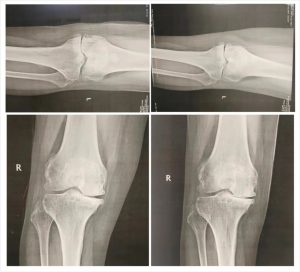

据了解,患者今年62岁,受右膝关节疼痛困扰达二十余年,随着病情加重,出现膝盖肿胀,不能屈曲,逐渐演变为“0”型腿,严重影响生活质量,多次辗转就医(多家省级医院),未见好转,经朋友介绍,来到我院骨科就诊。我院罗吉伟教授详细询问了患者病史,经检查诊断为原发性双侧膝关节病。

根据影像学资料所示,建议患者住院治疗,罗吉伟教授带领团队为其缜密制定手术方案,并成功实施右膝关节单髁置换术,术后第二天患者就能下地行走,患者膝关节疼痛明显缓解,膝关节功能逐渐恢复正常。